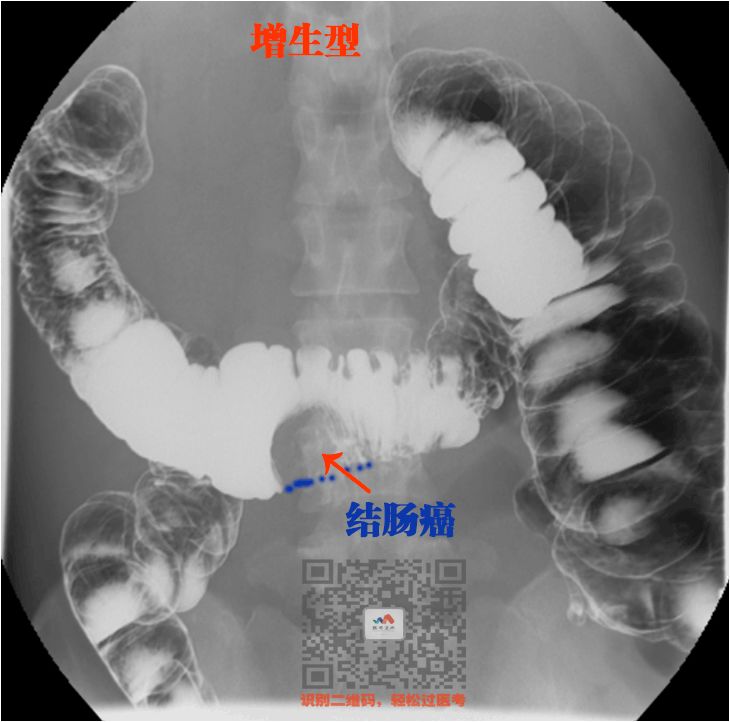

⑤ 结肠癌

结肠癌也跟胃癌一样

只是他发生在结肠

增生型表现为充盈缺损

(少了一块)

浸润型表现为肠腔狭窄

(一点点钡剂通过)

看图